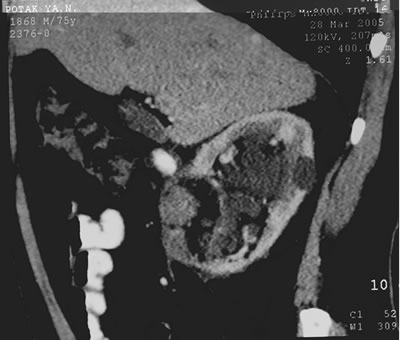

Спиральная

компьютерная томография (СКТ)

Правая почка: в передней

губе в среднем сегменте образование 37*35*23 мм, множественные

кисты диаметром до 20 мм и киста в верхнем сегменте

– 45*36*35 мм.

Левая почка: два образования 15 мм в верхнем

сегменте и 40 мм в среднем сегменте.

Фиброзная касула, регионарные л/у – интактны.